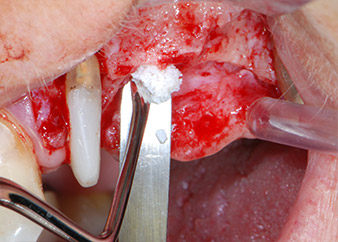

One month later, on the day of surgery, pain and inflammation at tooth 24 were minimal, but mobility of Miller class 2 was still present. After opening the flaps and cleaning the periapical and peri radicular infected tissue, the extent of the bone defect became obvious (Figs. 2 and 3).

total loss of bone and attachment

Fig. 2 and 3: After raising flaps, one month after endodontic revision and initiation of full-mouth periodontal therapy, the buccal root of tooth 24 showed a total loss of bone and attachment.

However, we maintained our initial plan to retain both teeth as temporary bridge abutments during the six-months osseointegration period of the implants. At reentry, the situation would have to be reassessed. First, in an attempt to manage the endo-perio problem, the remaining root surface was carefully debrided with piezoelectric equipment (Piezomed, W&H, used with the spatula-shaped insert S1, originally designed for erosion of the lateral sinus wall) (Fig. 4).